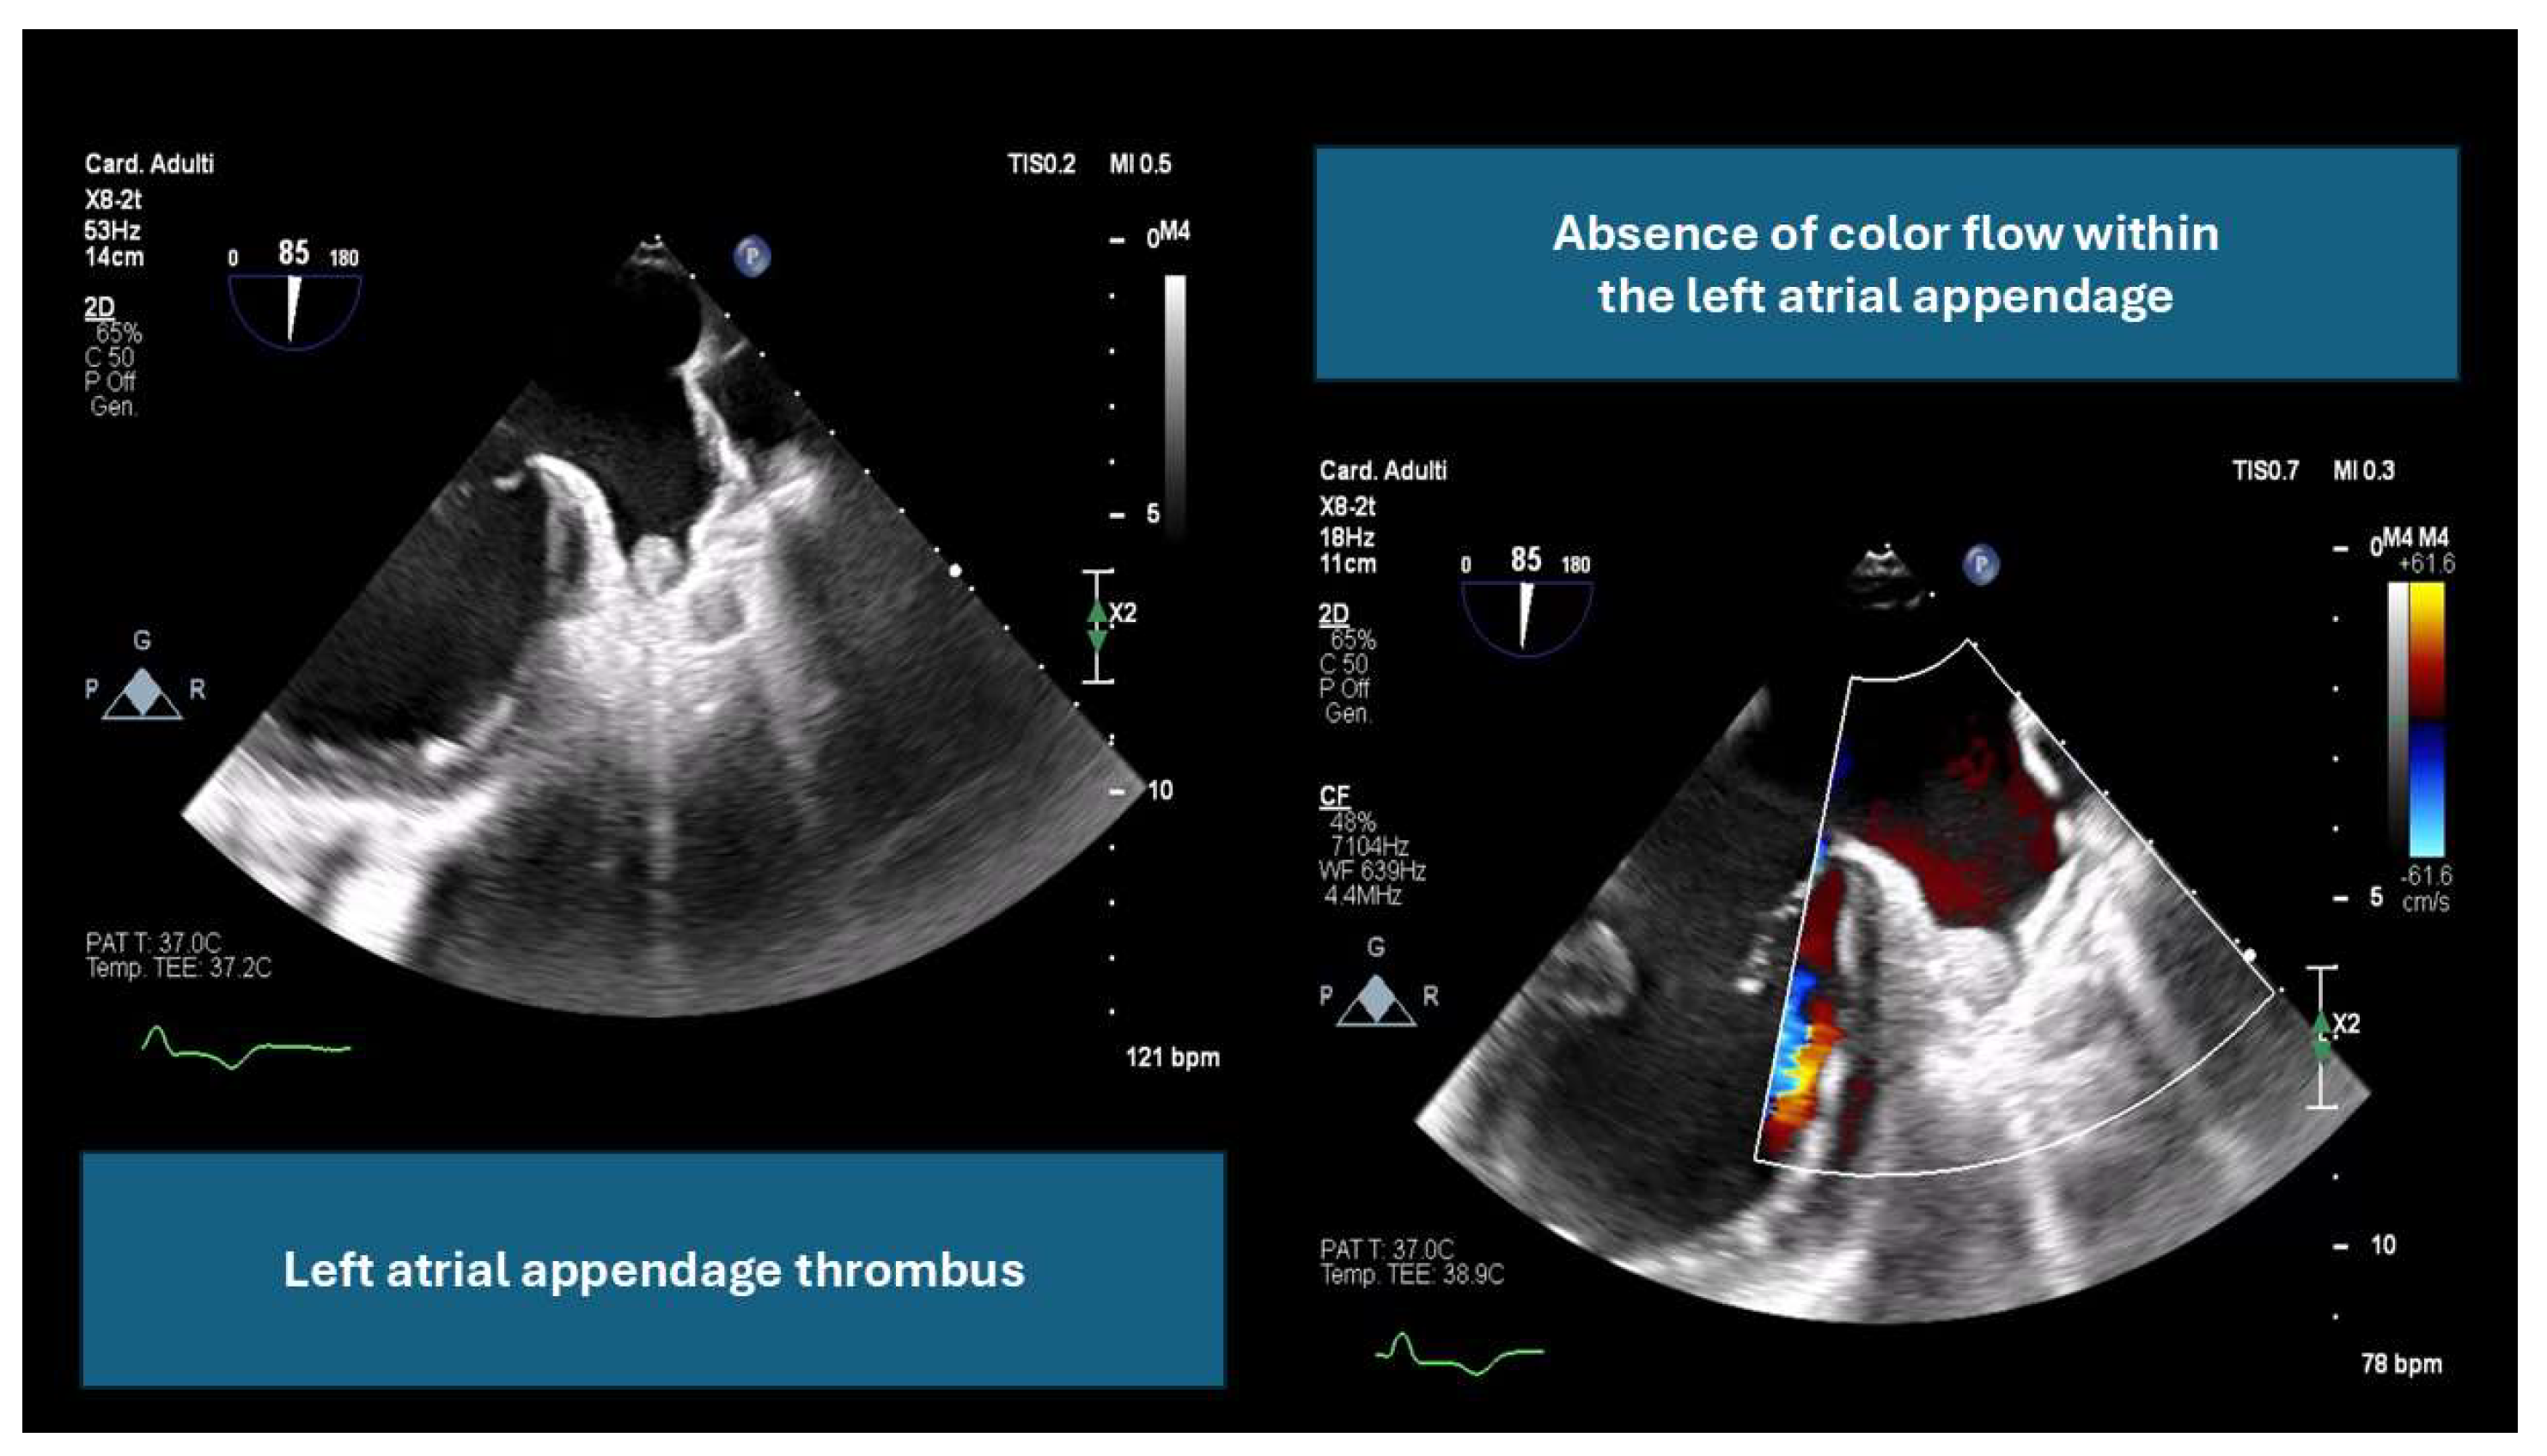

- By ruling out LAA thrombus, which can increase the risk of embolic events (an example is provided in Figure 1).